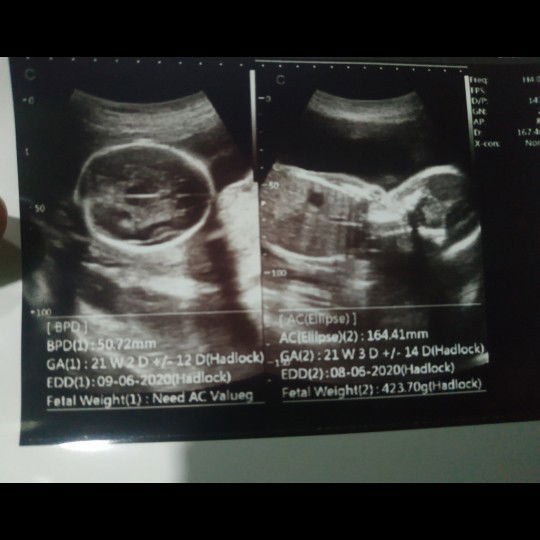

usg

Bun ada yg tau singkatan dari foto usg ini . Hehe maklum baru pertama